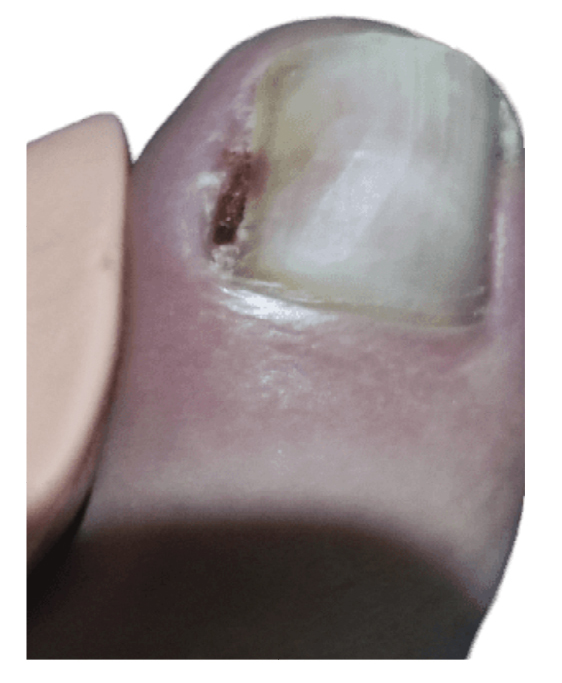

La paciente presenta inicialmente mejoría del dolor, aunque nunca termina de ceder completamente (Figura 4). Refiere recurrencia de la lesión ungueal lo que le lleva a consultar una segunda opinión a las 6 semanas de la intervención con otro podólogo. Este último con fecha 27 de diciembre (Figura 5) realiza cultivo bacteriano de la lesión, resultando negativo, y también valoración de la lesión mediante ecografía (sin informe). El 13 de enero la paciente es intervenida quirúrgicamente mediante técnica fenol-alcohol en el borde lateral del primer dedo del pie izquierdo (Figura 6).

Figura 5. Semana 16. Cultivo bacteriano negativo y valoración por ecografía (no disponible).